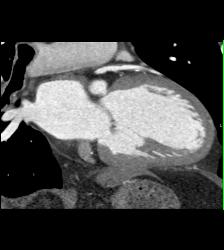

Dilated RCA After Reimplantation S/p Root Repair